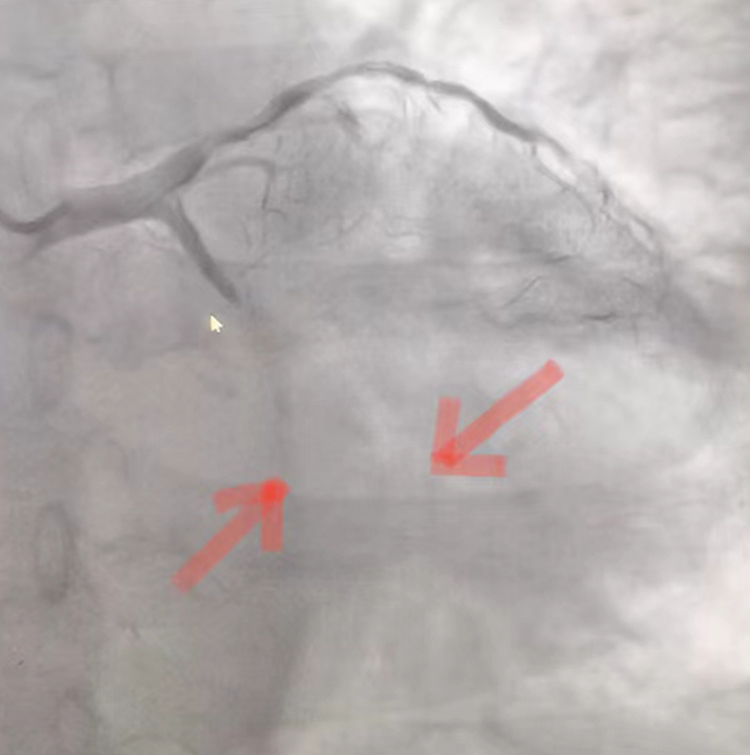

术前

术后

无独有偶,术后短暂休息时刻,又一位64岁突发急性心梗并心衰患者转入CCU,考虑到患者病情较重,副主任李雷再次投入战斗。在第一时间给予抗血小板、抗凝治疗的同时和家属沟通病情,联系导管室及我院介入团队邢建龙医生急行冠脉造影,显示患者冠脉三支重度病变,左冠弥漫性钙化,回旋支自近段100%急性闭塞,前降支近段80-90%狭窄,自中段100%慢性闭塞。病情危重,情况紧急!患者回旋支及前降支有急诊PCI指征,但术中可能出现恶性心律失常、低血压休克,甚至猝死可能,李主任再次和家属沟通病情,征得家属同意后签署相关知情同意书。事不宜迟!抢救仪器及药品就绪,立即追加肝素,沿桡动脉鞘管送EBU3.5指引导管至左冠开口,手术开始。9分钟后,导丝顺利通过旋支狭窄部位并应用硬球囊预扩完成,造影提示病变血管再灌注,借助支架精准定位技术,成功将一枚2.75×16mm支架植入旋支近段。球囊后扩后复查造影示支架展开良好。然而手术医生不敢有丝毫懈怠,继续乘胜追击,终将导丝通过前降支慢性病变并对其成功实施冠脉成形术,再次造影示冠脉无夹层、撕裂,前向血流通畅。29分钟后患者安返病房,后胸痛及憋喘症状逐渐缓解,心电图示心肌缺血明显改善。目前病人恢复良好,预计不久即可出院。